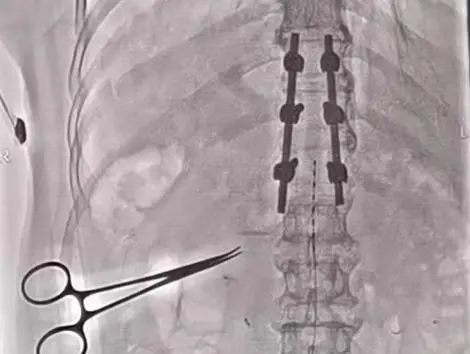

4月27日在医院复合手术室,由寿记新主任医师、管海博主治医师共同完成颈段及腰段短时程脊髓电极植入术,为患者尽早拔除气管套管、完全清醒、站起来、能走路、回归生活奠定了良好基础。

病例二:老年男性,1个月前“因高处坠落致颅脑及胸段脊髓损伤后双下肢截瘫”,由外院转入神经外科一病区,后经积极评估、讨论后给予胸段椎管扩大减压+内固定术。术后虽左下肢可稍活动,但右侧下肢仍无明显活动、大小便排便困难,需持续卧床,家属进行照顾。患者及家属治疗愿望迫切,1周前科室再次充分讨论下一步治疗方案,最后决定行腰段短时程脊髓电刺激手术治疗。